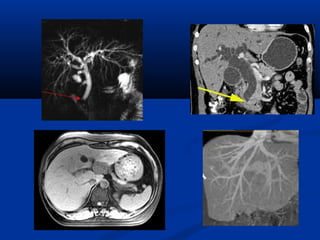

Diffusion Perfusion

Diffusion Tensor MRI

(DTMRI)

Choline vaø lactic acidPHOÅ COÄNG HÖÔÛNG

TÖØ

(SPECTROSCOPY/MRS)